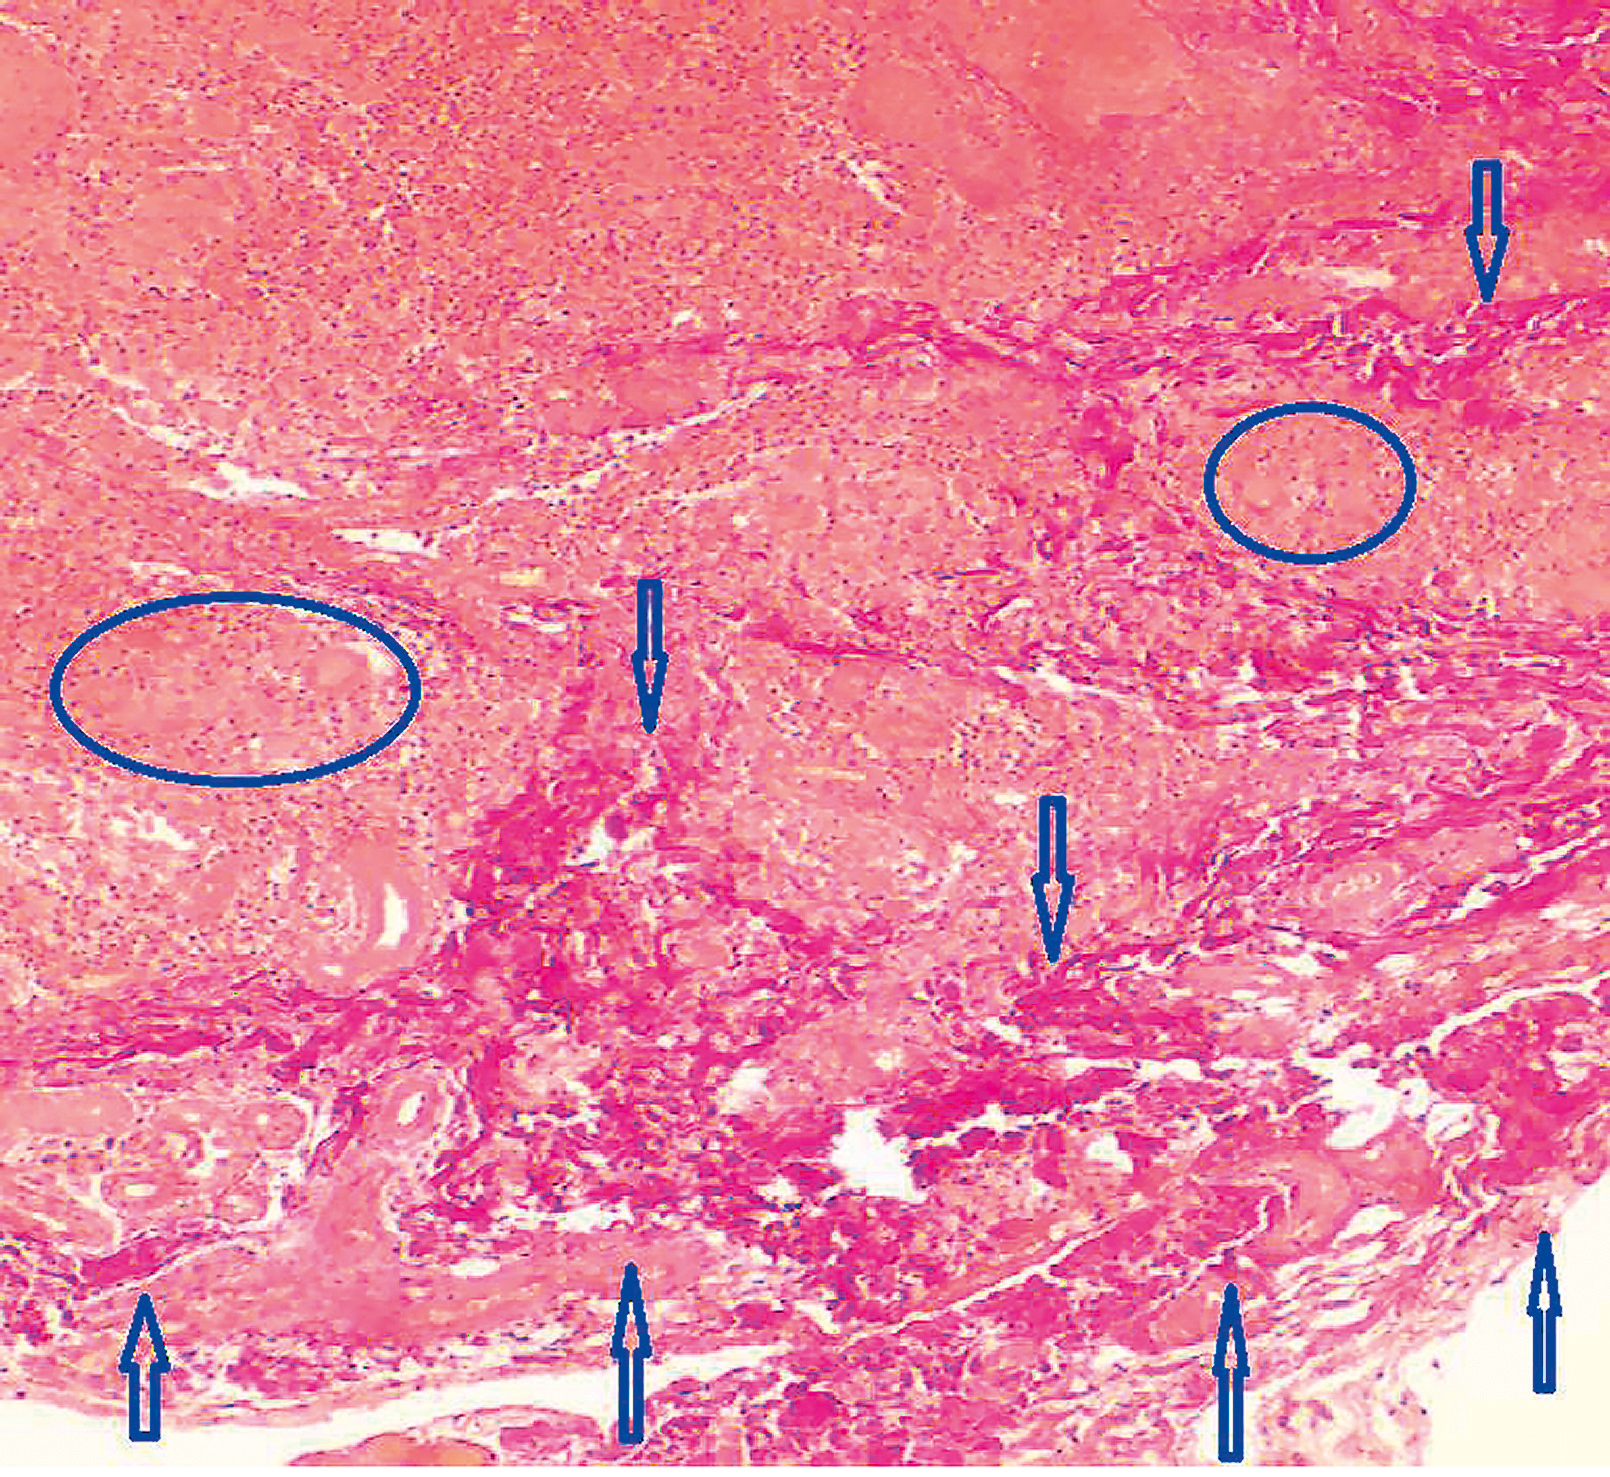

При проведении гистологического исследования пораженного участка кожи лица выявлены характерные признаки для гранулематозного дерматита: в фолликулах очаги некроза, макрофаги с примесью нейтрофильных лейкоцитов, единичных эозинофилов и гигантских многоядерных клеток (рис. 2). В глубоких слоях дермы определялись грубые, неравномерно утолщенные и местами разнонаправленные пучки коллагеновых волокон с признаками некроза и наличием гигантоклеточных гранулем (рис. 3), а также многочисленные гигантоклеточные гранулемы без некроза (рис. 4), экзоцитоз лимфоцитов, что характерно для гранулематозного дерматита.

Рис. 2. Гистологическое исследование кожи, окраска гематоксилином и эозином (×100). В фолликулах очаги некроза (обведены синим курсором), макрофаги с примесью нейтрофильных лейкоцитов, единичных эозинофилов и гигантских многоядерных клеток (указаны синей стрелкой)

Fig. 2. Histological examination of the skin, stained with hematoxylin and eosin (magnification ×100). In the follicles, there are foci of necrosis (circled with a blue cursor), macrophages with an admixture of neutrophilic leukocytes, single eosinophils, and giant multinucleated cells (indicated by a blue arrow)

Рис. 4. Гистологическое исследование кожи, окраска гематоксилином и эозином (×100). Многочисленные гигантоклеточные гранулемы без некроза (обведены синим курсором)

Fig. 4. Histological examination of the skin, stained with hematoxylin and eosin (magnification ×100). Numerous giant cell granulomas without necrosis (circled in blue)